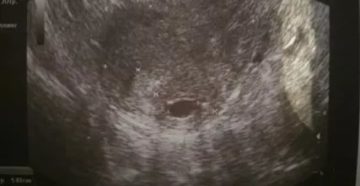

Причины неразвивающейся беременности пятница, мая 20, 2016 — 13:55 Плодным яйцом называется структура, окружающая эмбрион…